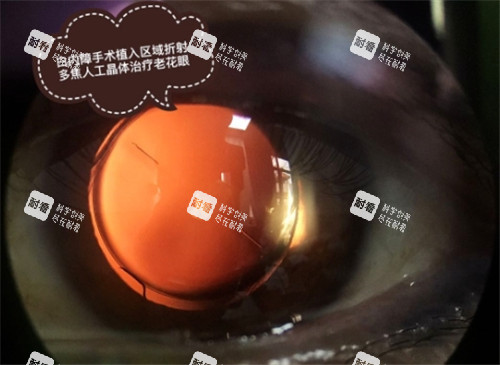

需要注意的是,飞秒激光、多焦点晶体等高端项目是需要全额自付的。